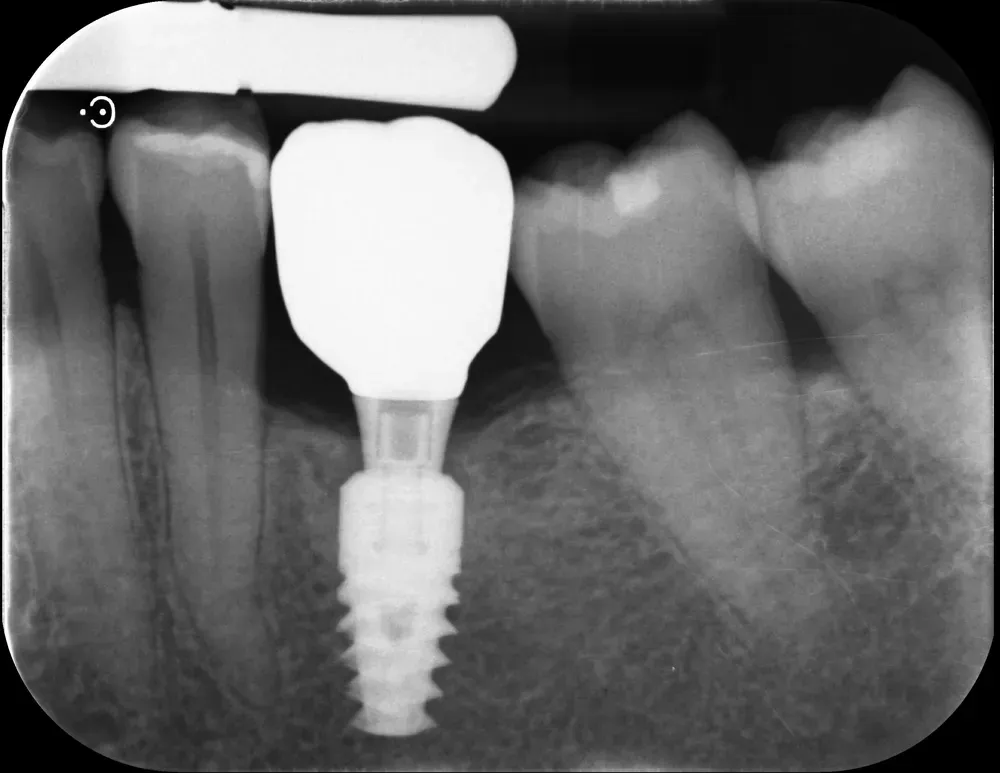

Sull’altezza: la review di Muñoz e collaboratori (https://doi.org/10.1111/clr.14025), basata solo su RCT, ha identificato una soglia di 2 mm. Abutment alti almeno 2 mm svolgono un ruolo protettivo contro la perdita ossea marginale, permettendo la formazione dell’adesione mucosale sovracrestale. Questo effetto appare indipendente dallo spessore dei tessuti molli, anche se in caso di tessuti sottili è importante posizionare gli impianti sottocrestali (o meglio, “infracrestali”) per consentire la formazione del complesso mucosale sovracrestale.

La regola dei 4mm di Linkevičius ci viene in aiuto per stabilire la posizione verticale che protegge l’impianto dal riassorbimento osseo, sempre nel caso di connessioni affidabili dal punto di vista batteriologico. Nelle prossime immagini, dei monconi protesici relativamente lunghi su impianti a connessione conica, testimoniano l’ottimo risultato reale di questo concetto, con impianti perfettamente integrati e privi di infiltrazione infiammatoria, anche in condizioni ossee impegnative.